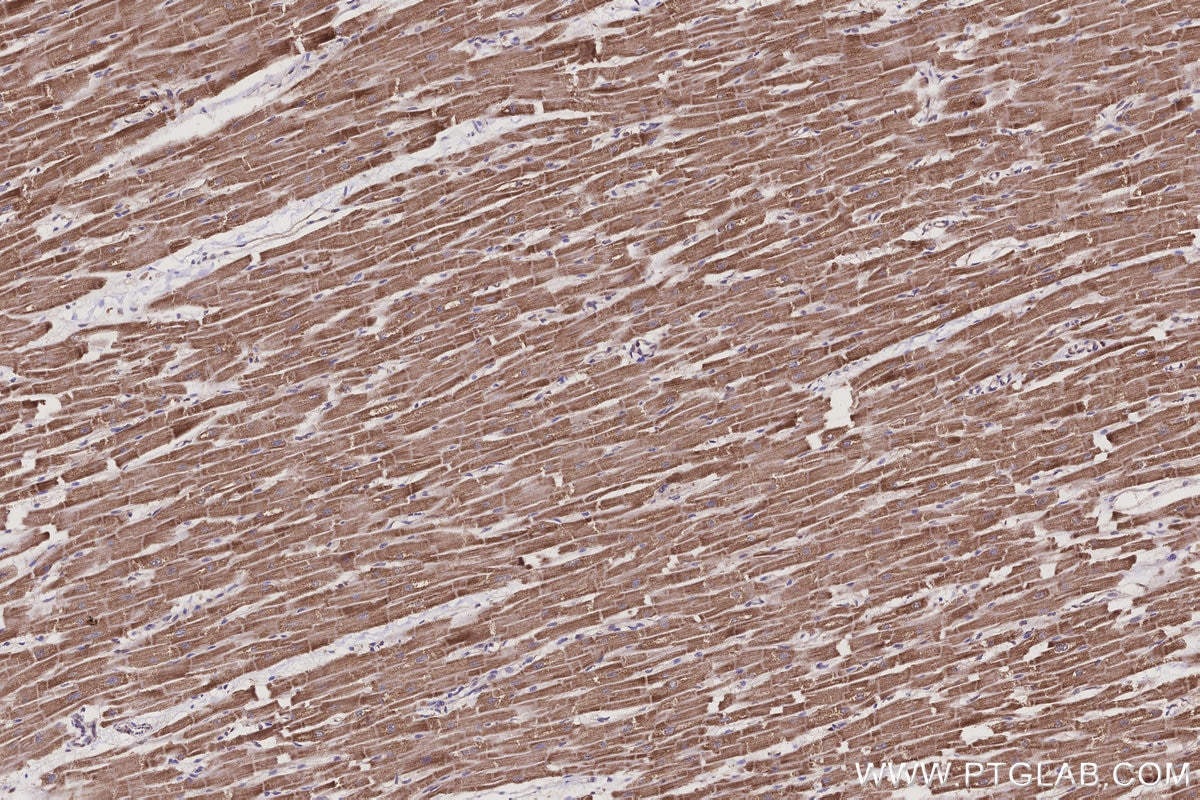

IHCeasy® CRAT Ready-To-Use IHC Kit

CRAT Ready-to-use reagent kit for IHC.

Validation Data Gallery

KHC3209 is a ready-to-use IHC kit for staining of CRAT. The kit provides all reagents, from antigen retrieval to cover slip mounting, that require little to no diluting or handling prior to use. Simply apply the reagents to your sample slide according to the protocol and you're steps away from obtaining high-quality IHC data.